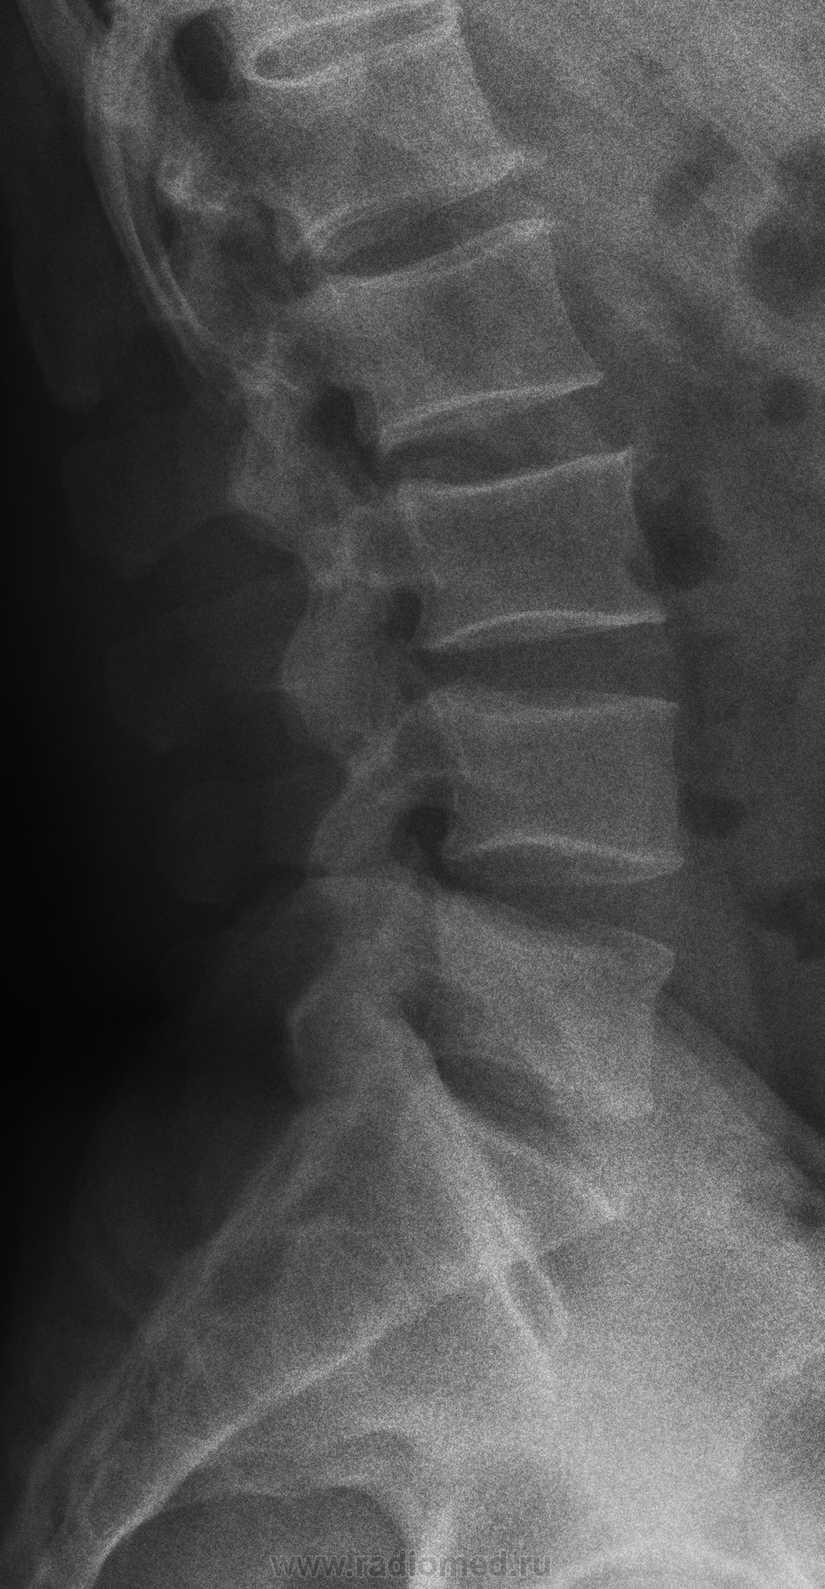

Медицинские снимки: рентген позвоночника сбоку